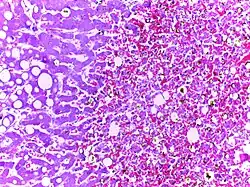

![]() | Tuberculous granuloma | Caseating granulomatous lesion with areas of amorphous granular eosinophilic necrotic debris known as caseation (on the right half) bordered by collections of epitheloid cells, Langhan giant cells and lymphocytes. | Category: Histopathology of tuberculous granuloma | Tuberculous granuloma |

![]() | Caseous necrosis | Caseating granulomatous lesion with areas of amorphous granular eosinophilic necrotic debris known as caseation (on the right half) bordered by collections of epitheloid cells, Langhan giant cells and lymphocytes. | Category: Histopathology of caseous necrosis | caseous necrosis |

![]() | Tuberculous lymphadenitis | Caseating granulomatous lesion with areas of amorphous granular eosinophilic necrotic debris known as caseation (on the right half) bordered by collections of epitheloid cells, Langhan giant cells and lymphocytes. | Category: Histopathology of tuberculous lymphadenitis | Tuberculous lymphadentis |